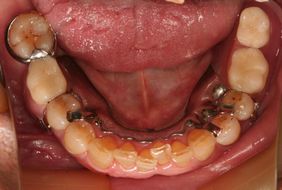

●テレスコープ式義歯(自費)

歯に直接つけられた内冠とそれに被さる外冠と入れ歯から構成されています。しっかりと固定され、口の中で入れ歯が動くことが少ないため、よく噛める。比較的修理しやすい。